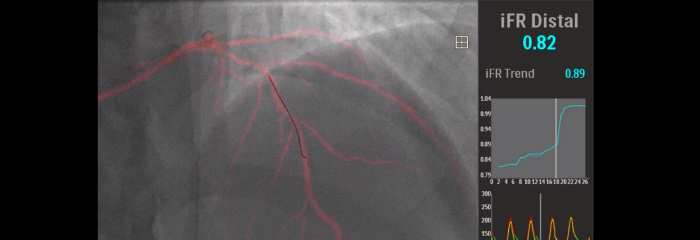

Image-guided therapy, iFR, IVUS and haemodynamic monitoring, as well as cardiac pre-procedure planning and advanced applications, are all connected to the image-guided therapy interface to allow viewing, manipulation and custom configuration on the monitor from a single controller at table side or from the control room.